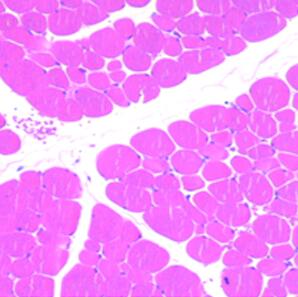

病理技術(shù)平臺——制片

北京蘭博泰斯生物科技有限公司在制備石蠟切片及冰凍切片方面有豐富的經(jīng)驗。

病理技術(shù)平臺——染色技術(shù)服務(wù)

北京蘭博泰斯生物科技有限公司以解決科研問題為目標(biāo),利用專業(yè)技術(shù)資源,為科研工作者提供醫(yī)學(xué)科研樣本檢測...